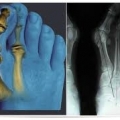

Диагноз не вызывает особых затруднений. Врач может диагностировать вальгусную деформацию большого пальца стопы уже при первом осмотре. Рентгенологическое обследование поможет установить характер костных деформаций, степень повреждения сустава и угловые отношения между первой и второй плюсневой костью. Следует назначить анализы крови и мочи для установления возможных метаболических нарушений.

В зависимости от степени деформации большого пальца стопы различают 4 стадии заболевания.

Лечение преимущественно симптоматическое, направленное на устранение болевого синдрома. При выраженных деформациях производится хирургическое вмешательство. Раннее оперативное лечение ведёт к профилактике артроза в первом плюсне-фаланговом суставе и более благоприятным исходам операции. Современные хирургические методы не разрушают сустав, сохраняя его подвижность и опороспособность.